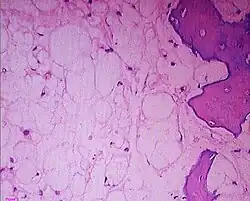

Histologic Subtypes

• Conventional

• Chondroid

• Better prognosis

• Subtype with predilection for skull base location

• Dedifferentiated